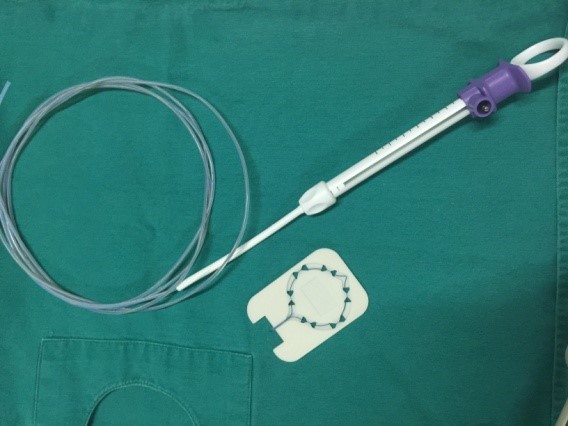

Hình ảnh Endoloop và dụng cụ thắt Endoloop

Kỹ thuật sử dụng vòng Endoloop để thắt cuống polyp lớn là một kỹ thuật được áp dụng tại Đơn vị nội soi Bệnh viện đa khoa tỉnh Hải Dương từ tháng 10 năm 2019. Với những tiến bộ trong các công cụ hỗ trợ nội soi hiện nay như Endoclips và Endoloops, nó đã trở nên an toàn hơn để thực hiện kỹ thuật nội soi cắt polyp cuống lớn. Cấu tạo của Endoloop gồm 2 phần: phần cán của Endoloop có cấu tạo gần giống như cán của thòng lọng, có bộ phận để đưa vòng Endoloop vào chân polyp, phần thứ 2 là vòng thắt được cấu tạo bằng chất dẻo đặc biệt có gắn thêm ống nhựa như một một cái khóa vòng thắt. Để ngăn ngừa chảy máu sử dụng dụng cụ Endoloop như một dây ga rô buộc chặt cuống polyp ở vị trí sát chân polyp trước khi tiến hành cắt bằng thòng lọng. Sau khi cắt polyp dụng cụ Endoloop vẫn còn lại vài ngày sau ở phần chân polyp cho đến khi phần này teo lại dụng vào lòng đại trực tràng.